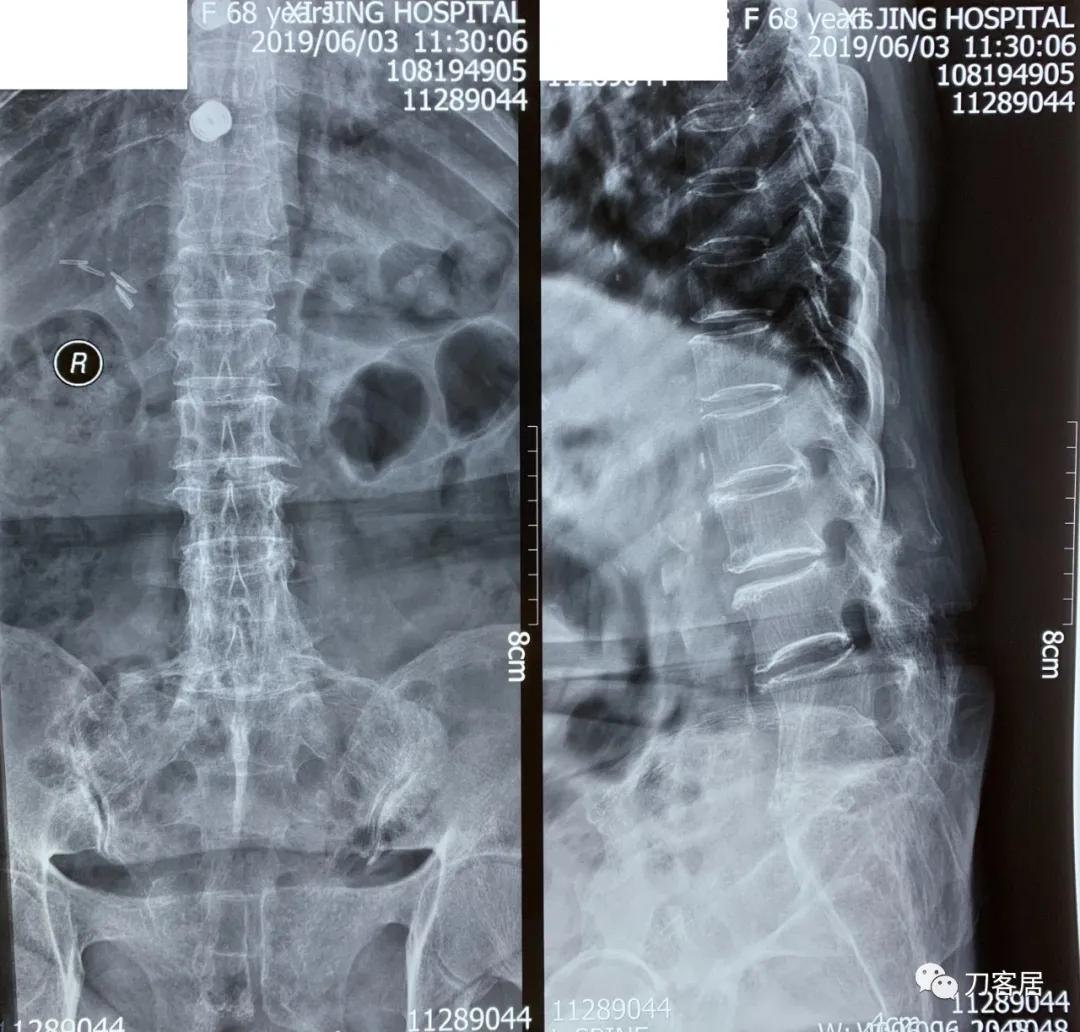

家属携带的影像学检查提示腰4-骶1病灶清除植骨融合术后改变,骨质疏松严重,未见椎旁脓肿以及结核病灶复发破坏。血沉、C反应蛋白化验检查结果正常。

诊断:腰4-骶1病灶清除植骨融合术后,严重骨质疏松症。

图1. 20190603西京医院腰椎正侧位X线片

图2. 20190603西京医院腰椎左右侧屈正位X线片